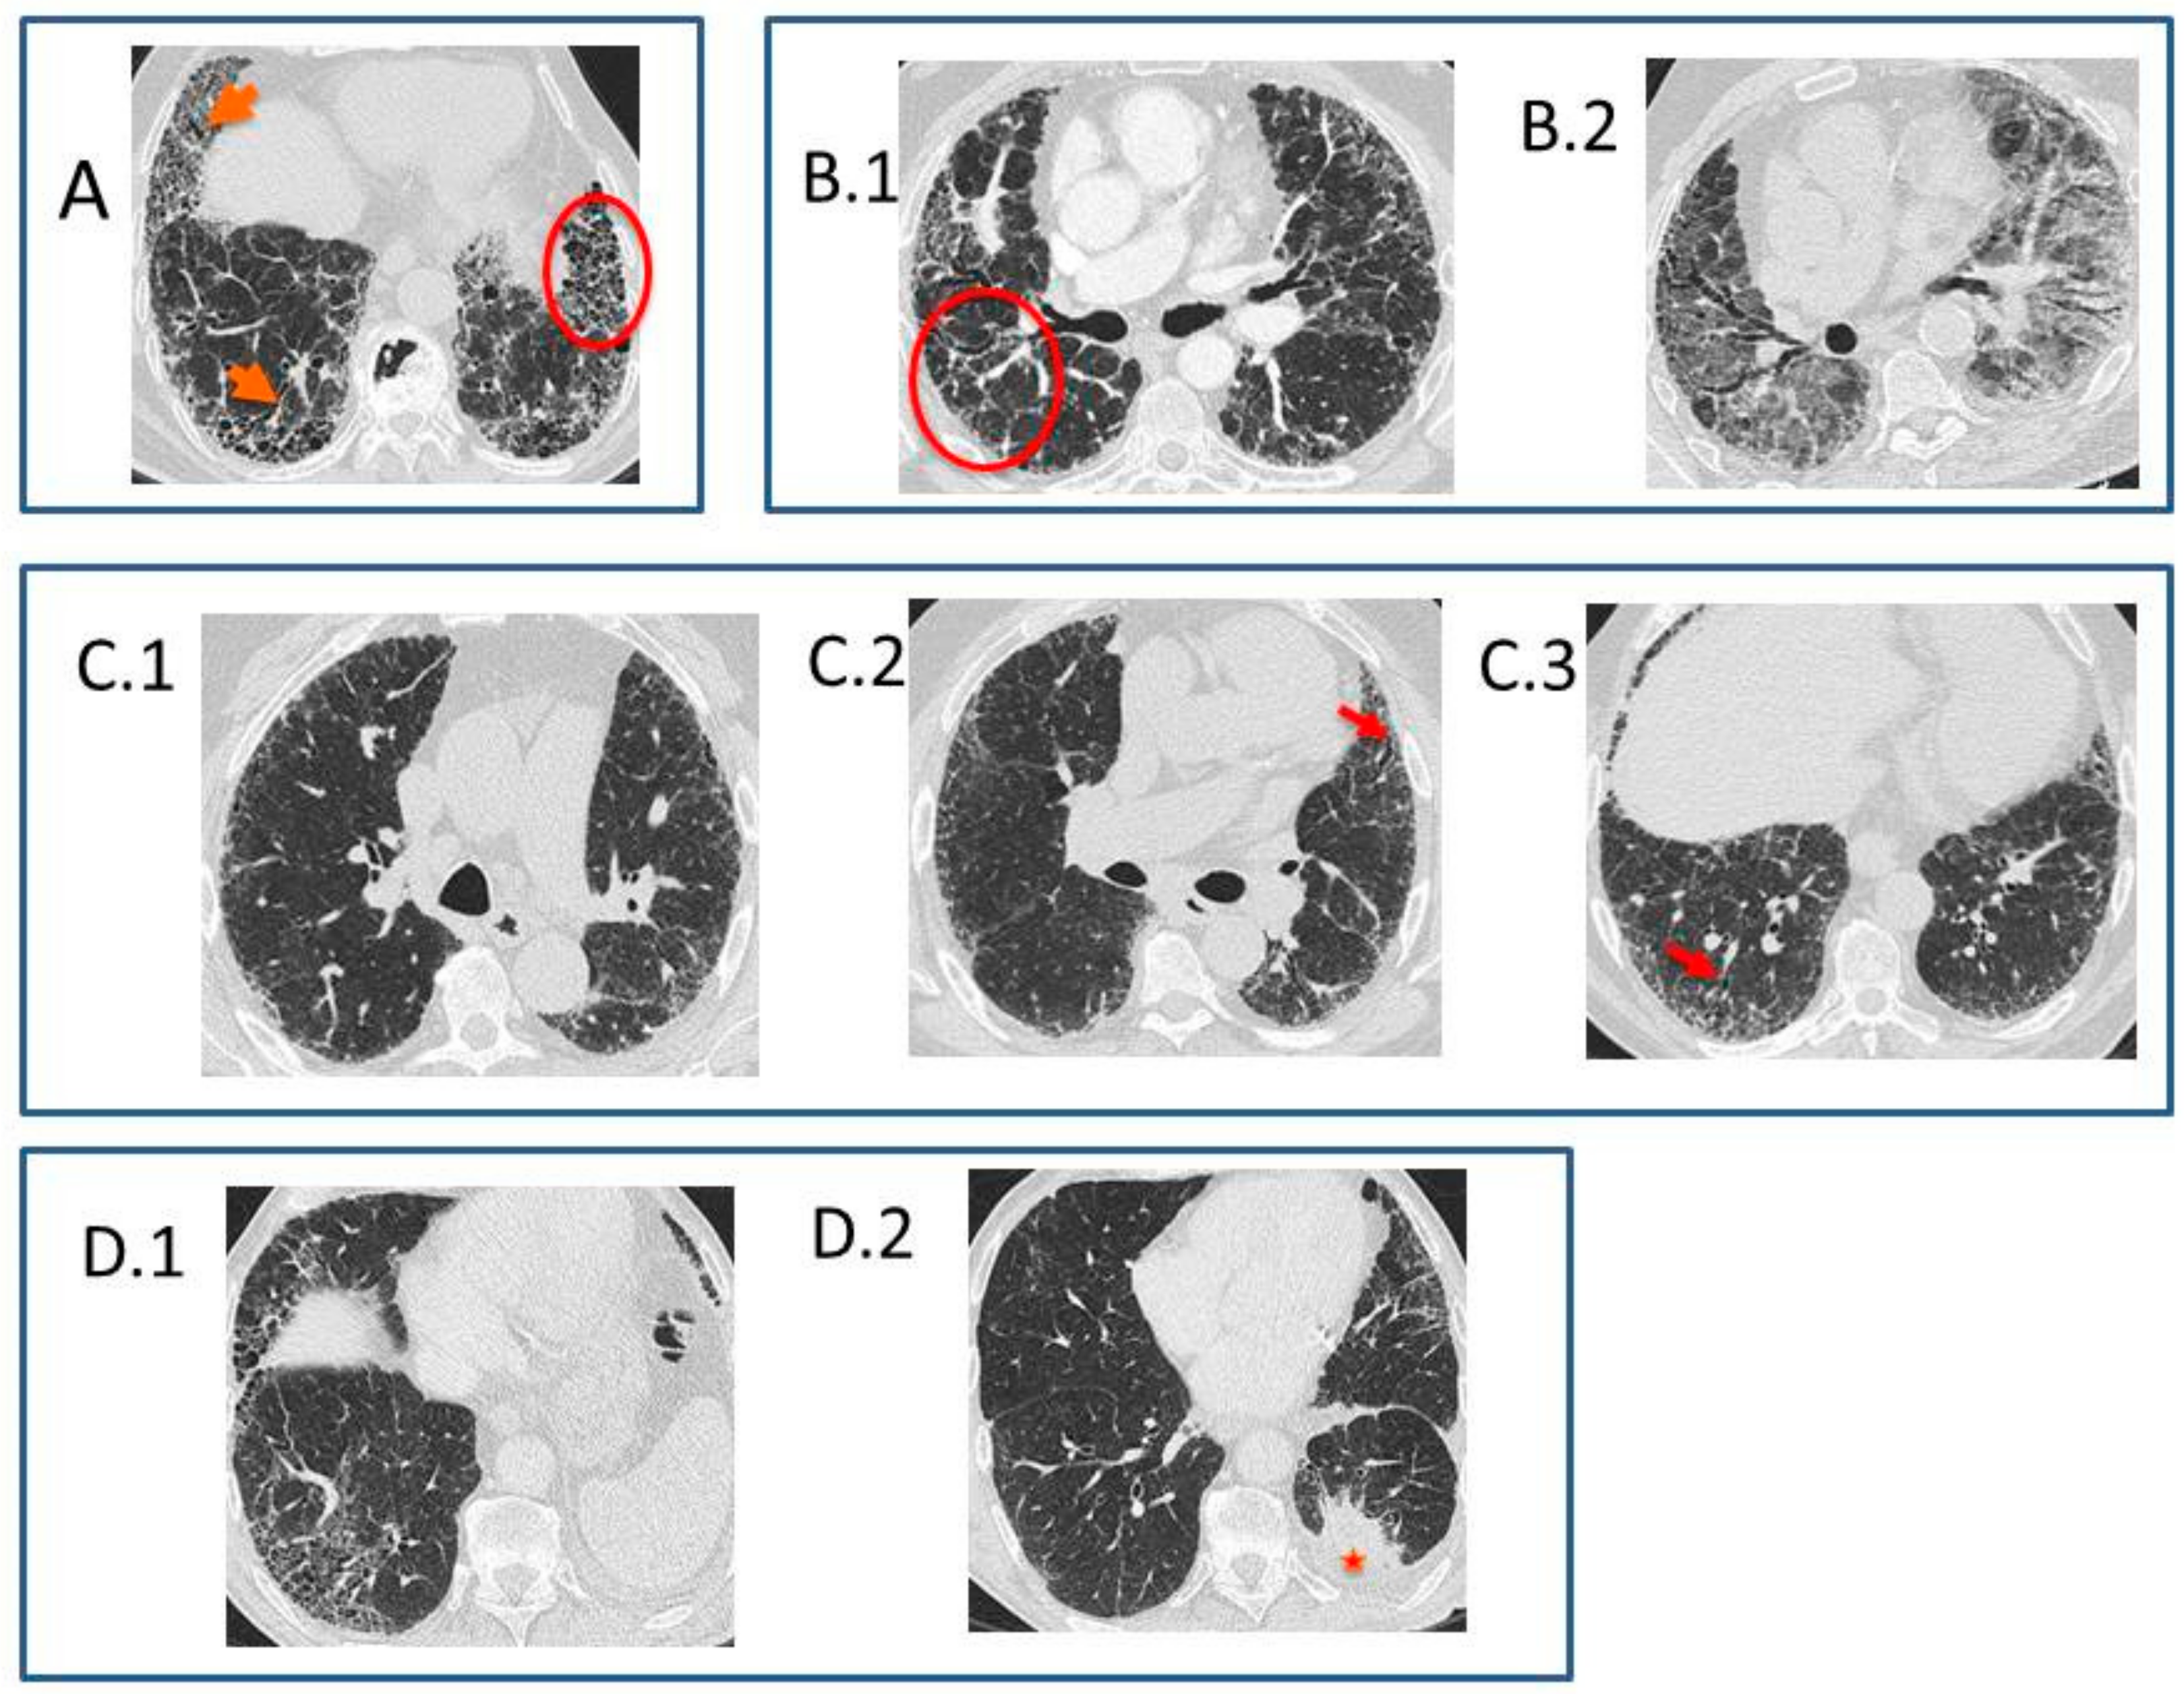

- Typical UIP CT pattern: Reticular opacities and honeycombing, with peripheral traction bronchiectasis and subpleural and basal-predominant distribution. Furthermore, there must be no other findings suggesting an alternative diagnosis (see below, Figure 2A). The fibrosis distribution can be asymmetric. This corresponds to the 2011 UIP pattern guidelines. To make an IPF diagnosis, a lung biopsy is not required in the correct clinical context and in the absence of a known cause of pulmonary fibrosis.

Figure 2. HRCT in IPF. (A) Typical UIP CT pattern. HRCT image: honeycombing (circle) and reticular opacities with peripheral traction bronchiectasis (arrows), with peripheral subpleural and basal-predominant distribution. (B) CT pattern indeterminate for UIP and acute exacerbation. (B.1) HRCT image: reticular abnormalities with traction bronchiectasis and non-basal predominance (circle). (B.2) HRCT image in left decubitus lateral six months after the previous examination: multifocal areas of ground glass opacities, overlapped with the previous pattern of pulmonary fibrosis. (C) Probable UIP CT pattern. (C.1–3) HRCT images: reticular pattern with traction bronchiectasis (arrows in C.2 and C.3) and a peripheral subpleural and basal predominance; peripheral reticulation is non-segmental (crossing fissures), heterogeneous, and present in upper lobes. Note that there is no honeycombing, and the UIP histological pattern was proven with pulmonary biopsy. (D) IPF and lung adenocarcinoma. (A,D.1) HRCT images: typical UIP CT asymmetrical pattern and lung mass in the apical segment of the left lower lobe (star in D.2). - Probable UIP CT pattern: Replaces the possible UIP pattern in the 2011 guidelines. It includes the same findings as the UIP pattern, although without honeycombing. A lung biopsy is not required in the correct clinical context and in the absence of a known cause of pulmonary fibrosis.

- CT pattern indeterminate for UIP: Appears when the fibrosis presents a variable or diffuse distribution or when there are inconspicuous findings suggesting a non-UIP pattern (Figure 2B). A lung biopsy is required to diagnose IPF in these patients.

In 2013, Gruden et al. [27] identified the HRCT findings—other than honeycombing—that appeared in patients with a biopsy-proved UIP. Subsequently [28], these findings were validated in a prospective cohort of 38 patients, with long-term clinical tracking. According to these authors, UIP diagnostic criteria in HRCT—in the absence of honeycombing—are as follows: (i) peripheral reticulation with lobular distortion, (ii) traction bronchiectasis and bronchiolectasis with or without honeycombing, (iii) basal predominance even with some affectation of the upper lobes, (iv) non-segmentary (i.e., without respecting the fissures) and heterogeneous (i.e., patched, alternating non-affected areas and correlated to the temporal and spatial heterogeneity of the histopathological UIP pattern), and (v) the absence of inconsistent findings, asymmetrical but non-unilateral (Figure 2C). The distinction between honeycombing and traction bronchiectasis does not affect the diagnostic accuracy of the CT if the criteria above are strictly verified. Therefore, the authors proposed that the IPF consensus guidelines should change the “honeycombing with or without traction bronchiectasis” criterion into “traction bronchiectasis with or without honeycombing”. This should allow more agreement across multiple observers, an earlier diagnosis of the disease—instead of the honeycombing in the latest stage as is the case when there is a UIP pattern—its applicability to patients whose comorbidities sometimes make surgical lung biopsy unavailable, and the possibility of benefiting from new antifibrotic drugs potentially effective in slowing fibrosis progression.

Presence of lung cancer can be suspected when a nodule or mass is observed in patients with pulmonary fibrosis, usually by the thickness of the fibrosis. The most frequent type is the adenocarcinoma, and the most frequent location is the lower lobes (Figure 2D) [32].

Acute exacerbation of IPF is an acute episode of clinical and functional respiratory worsening, with less than one month of evolution, with the presence in HRCT of bilateral ground glass opacities and/or consolidations over the underlying fibrosis pattern [33], in the absence of cardiac failure or fluid overload. It can appear in patients with known IPF or without a previous IPF diagnosis. It is due to the apparition of a histologic pattern of diffuse alveolar damage or organizing pneumonia over its histopathological UIP pattern. The cause can be unknown or there can be triggering factors, such as infection, aspiration, drugs, massive transfusion, and thoracic surgery, including the realization of a pulmonary biopsy or bronchoscopy. Although chest X-rays can show bilateral consolidations, patient evaluation must be made using HRCT whenever possible. In HRCT, areas of ground glass opacities, with or without consolidations, peripherical, multifocal, or diffuse, overlapped with the previous patterns of pulmonary fibrosis can be observed [34]. Radiologically, pulmonary causes of acute exacerbation, such as infection, extra-pulmonary and pulmonary embolism (which is the reason that HRCT must be done with endovenous contrast and angiographic techniques), pneumothorax, and pleural effusion, should be excluded. The prognostic is poor, with 50% patient mortality [35].